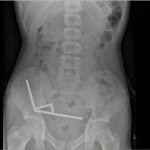

Połknął 200 magnesów z Temu. Ledwo to przeżył

13-letni chłopiec z Nowej Zelandii trafił do szpitala z pozornie zwykłym bólem brzucha. Kiedy jednak przyznał, że połknął "ze sto magnesów", lekarze z Tauranga Hospital natychmiast...magnesy -